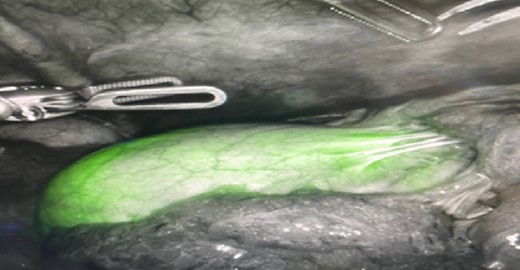

In the peri-operative period, a bolus ICG solution (2.5 mg in 10 mL of sterile saline) was administered intracystically via percutaneous cholecystostomy drain within 1 hour of the operative start time. An infra-umbilical incision was made, and a Hasson trocar was placed and insufflated with 15 mmHg of carbon dioxide. A laparoscope was inserted to inspect the abdomen. An 8 mm 30-degree laparoscope was introduced, and three additional 8 mm trocars were placed, one in the epigastrium and two in the right upper quadrants. Laparoscopic near-infrared cholangiograms were captured using the Firefly system on the DaVinci robot, as demonstrated in Figs 2 and 3A and B and 4A) with Fig. 4B displaying the gallbladder fossa after removal.

Initial illumination of gallbladder after ICG injection through PCDC.